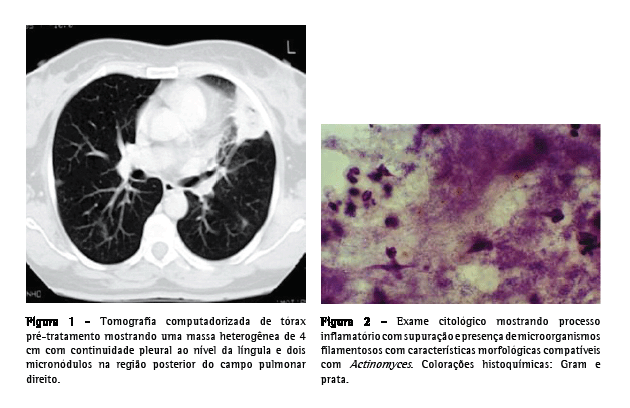

Uma paciente do sexo feminino, 55 anos de idade, caucasiana, não fumante, secretária, procurou atendimento no serviço de emergência. Tinha história de hepatite B crônica, hipertensão arterial, dislipidemia mista e múltiplas cáries dentárias não tratadas. Relatou que há três semanas havia iniciado quadro de dejeções diarréicas diárias, azia, desconforto retroesternal agravado pelo decúbito dorsal, astenia, anorexia e emagrecimento (5 kg). Uma semana depois haviam surgido toracalgia esquerda de características pleuríticas com agravamento progressivo, acessos freqüentes de tosse seca ao esforço e pico febril isolado. O eletrocardiograma foi normal, e a endoscopia digestiva alta revelou um cárdia complacente e gastrite antral. A telerradiografia de tórax mostrou hipotransparência heterogênea, esboçando perda de substância em seu seio, no terço médio do campo pulmonar esquerdo. A tomografia computadorizada de tórax evidenciou a presença de uma massa de 4 cm com conteúdo heterogêneo e continuidade pleural ao nível da língula e a presença de dois micronódulos subpleurais na região posterior do campo pulmonar direito (Figura 1). Procedeu-se ao estudo etiológico considerando-se a hipótese diagnóstica de neoplasia pulmonar como a mais provável. Do estudo analítico, salientam-se os seguintes resultados: velocidade de hemossedimentação = 98 mm/1a h; antígeno do câncer 125 = 63,3 U.mL-1 (<35,0); antígeno carcinoembriogênico = 3,55 ng.mL-1 (<2,5) e discreta elevação da proteína C reativa. O estudo imunológico sérico, os marcadores virais e o estudo analítico final não revelaram outras alterações relevantes. Os resultados da colonoscopia, da ultrassonografia abdominopélvica, da mamografia e da citologia cérvico-vaginal foram normais. A primeira fibrobroncoscopia realizada mostrou sinais inflamatórios difusos ao nível da língula. Os resultados do exame citológico de aspirado, lavado brônquico e lavado broncoalveolar foram negativos para células neoplásicas. O exame microbiológico em aerobiose foi também negativo, assim como a pesquisa de bacilos álcool-ácido resistentes. A paciente foi então submetida à biópsia aspirativa transtorácica (BAT), que, ao exame citológico extemporâneo, mostrou um processo inflamatório com supuração. Face a este resultado provisório, iniciou-se a antibioticoterapia com levofloxacina 500 mg via oral ao dia, e decidiu-se realizar uma segunda fibrobroncoscopia. Entretanto, o exame citológico da BAT revelou aspectos morfológicos compatíveis com a presença de Actinomyces, confirmada pelo exame microbiológico cultural do lavado brônquico e broncoalveolar da segunda fibrobroncoscopia, no qual se identificou A. naeslundii (Figura 2). A pesquisa de bacilos álcool-ácido resistentes foi negativa. Dada a melhoria clínica e radiológica após um mês de tratamento (Figura 3), optou-se por manter a antibioticoterapia já iniciada, cuja posologia foi alterada: levofloxacina 500 mg endovenoso ao dia por quatro semanas e, depois, 500 mg po qd. Não se verificou iatrogenia à terapêutica, a qual foi mantida por 16 semanas, até a completa normalização radiológica. Analiticamente constatou-se uma redução da velocidade de hemossedimentação e uma redução de ambos os marcadores tumorais inicialmente alterados, assim como a normalização da proteína C reativa. A paciente foi também submetida a tratamento dentário.